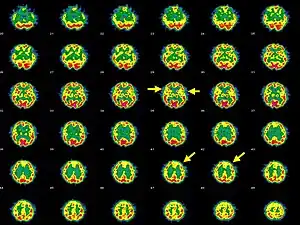

| Brain SPECT transaxial images of a patient afflicted with Hashimoto's encephalopathy. | |